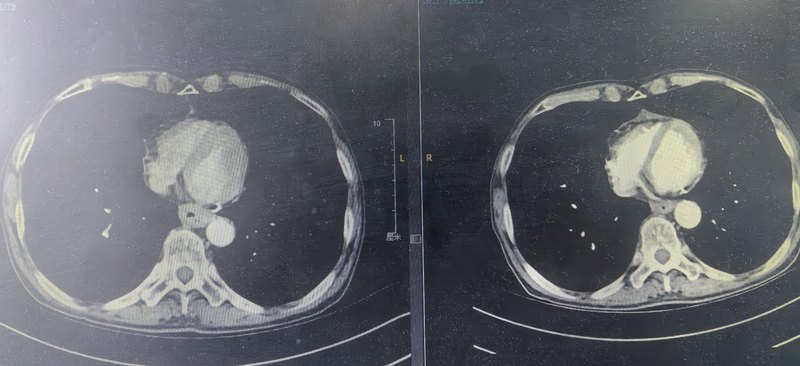

??在大眾普遍認(rèn)知里,食管癌一旦確診,大刀闊斧的外科手術(shù)往往被視為首要選擇。然而,對于部分特殊患者而言,傳統(tǒng)外科手術(shù)卻可能是難以逾越的“天塹”。?在食管癌的治療領(lǐng)域,內(nèi)鏡下全層切除手術(shù)作為一項極具創(chuàng)新性的技術(shù),正逐漸嶄露頭角。然而,這一手術(shù)的難度系數(shù)極高,對醫(yī)生的技術(shù)水平、經(jīng)驗積累以及醫(yī)院的綜合實力都有著近乎苛刻的要求。在眾多醫(yī)療工作者中,復(fù)旦大學(xué)附屬中山醫(yī)院內(nèi)鏡中心的鐘蕓詩教授,憑借其精湛的醫(yī)術(shù)和豐富的經(jīng)驗,在這一高難度手術(shù)領(lǐng)域取得了令人矚目的成就,成功為這類患者開辟出一條生命新通道,實現(xiàn)了既挽救生命又保留食管的雙重奇跡。??71歲的趙女士,命運的軌跡布滿坎坷。20年前,左側(cè)乳腺癌初次來襲,外科手術(shù)與放療的痛苦她咬牙扛過。此后,闌尾炎、肺結(jié)節(jié)、腸粘連伴小腸梗阻等病癥輪番折磨,多次手術(shù)讓她的身體愈發(fā)虛弱。10年高血壓病史,依靠纈沙坦控制血壓,生活剛稍有喘息,新的危機卻悄然降臨。??半年前,趙女士進(jìn)食時莫名出現(xiàn)哽噎感,飯后還偶有反酸、燒心,雖癥狀能自行緩解,卻像陰霾籠罩心頭。前往外院檢查,結(jié)果令人揪心:食管PET-CT檢查顯示食管上段FDG攝取增高,高度懷疑惡性腫瘤;胃鏡檢查發(fā)現(xiàn)食管隆起型糜爛,位置極為特殊,在距門齒18-22cm的高位食管處,病理確診為鱗狀上皮高級別瘤變并癌變;超聲內(nèi)鏡進(jìn)一步揭示,病灶處粘膜層增厚,部分與粘膜下層融合,甚至累及固有肌層。??面對這一診斷,當(dāng)?shù)蒯t(yī)院的醫(yī)生告訴她,就該病而言,傳統(tǒng)外科手術(shù)是常規(guī)治療手段,但趙女士的身體狀況卻讓這條路被徹底堵死。她體質(zhì)差,多次手術(shù)史及多種復(fù)雜合并癥,使她根本無法承受外科手術(shù)帶來的巨大創(chuàng)傷。就在趙女士幾乎陷入絕境之時,她的遠(yuǎn)房親戚帶給她了一線希望,向她推薦了器官保留專家復(fù)旦大學(xué)附屬中山醫(yī)院內(nèi)鏡中心副主任鐘蕓詩教授。她慕名來到復(fù)旦大學(xué)附屬中山醫(yī)院內(nèi)鏡中心,找到了鐘教授。??鐘蕓詩教授領(lǐng)銜的器官保留MDT團(tuán)隊,經(jīng)過全面、細(xì)致、嚴(yán)謹(jǐn)?shù)男g(shù)前評估,鑒于趙女士的特殊情況,團(tuán)隊制定了先化療及免疫治療的方案,如果治療有效,病灶退縮,再綜合評估是否有內(nèi)鏡下切除機會。兩個療程治療后,顯著效果令人振奮:CT復(fù)查顯示食管腫瘤明顯縮??;再次胃鏡復(fù)查,原病灶隆起消失,僅留不規(guī)則瘢痕樣改變,活檢病理提示炎癥改變,超聲內(nèi)鏡也顯示出腫瘤相關(guān)退縮的變化。此時,趙女士迫切希望可以通過內(nèi)鏡切除食管病灶。要知道,趙女士的病灶,在高位食管這個特殊位置,并且是疤痕樣改變,普通內(nèi)鏡下粘膜下剝離的方法,有可能對趙女士來說不能達(dá)到根治效果。種種要素,增加了手術(shù)難度,難度堪稱“在針尖上跳舞”。MDT團(tuán)隊再次討論后,鐘蕓詩教授憑借其精湛的內(nèi)鏡技術(shù),毅然決定挑戰(zhàn)這一高難度手術(shù),鐘教授決定為趙女士實施內(nèi)鏡下全層切除術(shù)。??鐘蕓詩教授作為復(fù)旦大學(xué)附屬中山醫(yī)院內(nèi)鏡中心的副主任,在消化內(nèi)鏡領(lǐng)域有著深厚的造詣和豐富的臨床經(jīng)驗。他長期致力于食管癌內(nèi)鏡下治療的研究和實踐,對內(nèi)鏡下全層切除手術(shù)有著獨到的見解和精湛的技術(shù)。在鐘蕓詩教授看來,內(nèi)鏡下全層切除手術(shù)不僅僅是一種技術(shù),更是一種對患者負(fù)責(zé)的態(tài)度,既要實現(xiàn)腫瘤的根治,又盡量減少創(chuàng)傷,在完整切除病灶的同時,最大限度保留食管功能、保留器官,患者術(shù)后恢復(fù)也快,生活質(zhì)量較高。鐘教授在手術(shù)前,會對患者的病情進(jìn)行全面、細(xì)致的評估,制定出最適合患者的手術(shù)方案;在手術(shù)過程中,他會憑借自己高超的技術(shù)和豐富的經(jīng)驗,小心翼翼地操作內(nèi)鏡,確保手術(shù)的安全和成功;在手術(shù)后,他還會密切關(guān)注患者的恢復(fù)情況,及時給予患者相應(yīng)的治療和指導(dǎo)。???復(fù)旦大學(xué)附屬中山醫(yī)院的內(nèi)鏡中心,患者迎來了關(guān)鍵的內(nèi)鏡切除手術(shù)——EFTR。手術(shù)過程中,鐘蕓詩教授展現(xiàn)出了卓越的技術(shù)優(yōu)勢。鐘教授結(jié)合放大內(nèi)鏡、超聲內(nèi)鏡,仔細(xì)觀察病變退縮范圍,精準(zhǔn)標(biāo)記切除區(qū)域,確保范圍大于殘余瘢痕,為徹底清除病灶奠定基礎(chǔ);緊接著,鐘教授沿標(biāo)記點在粘膜層和粘膜下層切開病灶邊緣,逐步切開并分離固有肌層,巧妙地分開肌層和外膜間隙,實現(xiàn)病灶的全層切除。最后,鐘教授用帶鼻固定線的全覆膜食管支架覆蓋創(chuàng)面。整個手術(shù)一氣呵成。術(shù)后病理結(jié)果更是令人欣喜:鱗狀上皮輕度異性增生,未查見腫瘤細(xì)胞,切緣陰性,手術(shù)大獲成功!后續(xù)鐘教授MDT團(tuán)隊繼續(xù)為趙女士制定免疫治療維持方案,如今她正常吃飯說話,生活質(zhì)量零影響。??目前這位患者,飲食、生活和患病前幾乎沒有太大區(qū)別,這一切都得益于鐘教授團(tuán)隊這種綜合的器官保留治療方案,成功達(dá)到了器官保留的目的,避免了傳統(tǒng)手術(shù)對身體的巨大創(chuàng)傷。正如鐘蕓詩教授所說,“而我們不僅要救命,更要讓患者有尊嚴(yán)地活著!我們追求的不只是腫瘤消失,更是患者重新綻放的笑容!”???復(fù)旦大學(xué)附屬中山醫(yī)院內(nèi)鏡中心鐘蕓詩教授團(tuán)隊,面對高位食管癌這一棘手難題,突破傳統(tǒng)治療局限,通過化療、免疫治療與內(nèi)鏡微創(chuàng)技術(shù)的精妙結(jié)合,成功解決了傳統(tǒng)外科手術(shù)無法攻克的困境。既避免了外科手術(shù)對患者身體的巨大創(chuàng)傷,又憑借高超內(nèi)鏡技術(shù)完美切除病灶,保住了患者的食管,維護(hù)了患者的生活質(zhì)量與尊嚴(yán)。這些成功案例,無疑為眾多身處絕境的食管癌患者點亮了希望之光,指引了新的求生方向。??隨著腫瘤免疫新時代的到來,免疫治療的加入,為術(shù)前新輔助治療在進(jìn)展期食管癌病人“器官保留”策略中的應(yīng)用,提供了充分的可行性。國內(nèi)外的多項研究證實,部分(30-40%)食管鱗癌病人在行新輔助放化療聯(lián)合免疫治療后,腫瘤能夠完全退縮,專業(yè)術(shù)語為“臨床完全緩解”。對于達(dá)到臨床完全緩解的食管癌病人,經(jīng)過內(nèi)鏡切除及病理評估后,若無腫瘤細(xì)胞殘留,僅需接受免疫維持治療。這樣做不僅能通過微創(chuàng)手段完全祛除病灶,降低治療后的復(fù)發(fā)率,還能夠在保存食管功能的同時保證長期生存質(zhì)量,這種治療策略即為“器官保留”策略。??當(dāng)然,并非所有的病人在接受新輔助治療后病灶都能完全退縮,但有研究表明,食管癌遵循了“肌層-黏膜下層-黏膜層”的退縮模式,即在多數(shù)病例中,殘留的腫瘤細(xì)胞位于食管黏膜層或黏膜下層,僅少部分腫瘤細(xì)胞留存于更深的肌層。此時內(nèi)鏡治療便發(fā)揮了其作用,不論是針對淺表病變的內(nèi)鏡下黏膜切除術(shù)(EMR)和內(nèi)鏡下黏膜下剝離術(shù)(ESD),還是適當(dāng)增加切除深度的內(nèi)鏡下全層切除術(shù)(EFTR),均可以做到病灶的完整切除,同時最大程度地保留了食管的結(jié)構(gòu)和功能。因此,鐘蕓詩教授的食管腫瘤MDT團(tuán)隊提出,如果在新輔助放化療聯(lián)合免疫治療后,對達(dá)到臨床完全緩解或近臨床完全緩解病人的初始腫瘤部位進(jìn)行完整內(nèi)鏡下切除,將會降低局部復(fù)發(fā)率,同時病人的長期生存率以及生活質(zhì)量將進(jìn)一步提高,從而達(dá)到“治愈腫瘤”與“保留器官”的兩全其美。??復(fù)旦大學(xué)附屬中山醫(yī)院內(nèi)鏡中心鐘蕓詩教授團(tuán)隊,對于新輔助放療、化療、免疫治療聯(lián)合內(nèi)鏡下切除術(shù),綜合治療食管癌,已經(jīng)積累了豐富的臨床經(jīng)驗。既免除了患者的手術(shù)之苦(不開刀),又保留了食管的完整性及正常生理功能,更重要的是患者的長期生存情況不受影響,生活質(zhì)量十分滿意。讓食管癌的病人保食管、保功能成為現(xiàn)實。專家介紹??鐘蕓詩教授,復(fù)旦大學(xué)附屬中山醫(yī)院內(nèi)鏡中心副主任,教授,博導(dǎo)。中國臨床腫瘤學(xué)會(CSCO)理事,中國抗癌協(xié)會消化道息肉及癌前病變專業(yè)委員會副主任委員,中國人體健康科技促進(jìn)會腸息肉防治專業(yè)委員會副主任委員,中國抗癌協(xié)會大腸癌專業(yè)委員會TEM學(xué)組副組長,中國醫(yī)師協(xié)會結(jié)直腸腫瘤專業(yè)委員會經(jīng)肛門微創(chuàng)手術(shù)專業(yè)學(xué)組、早診早治學(xué)組副組長,世界內(nèi)鏡醫(yī)師協(xié)會消化內(nèi)鏡微創(chuàng)聯(lián)盟理事長,中華消化內(nèi)鏡學(xué)會大腸鏡學(xué)組委員,上海市抗癌協(xié)會消化內(nèi)鏡專業(yè)委員會秘書長,上海市消化內(nèi)鏡學(xué)會委員兼任大腸鏡學(xué)組副組長。??主要從事消化道腫瘤的內(nèi)鏡治療和基礎(chǔ)研究。在國際上較早開展并熟練掌握包括ESD、EFTR、EUS、ERCP等各種內(nèi)鏡診療操作。專家門診時間:周一下午,周四上午